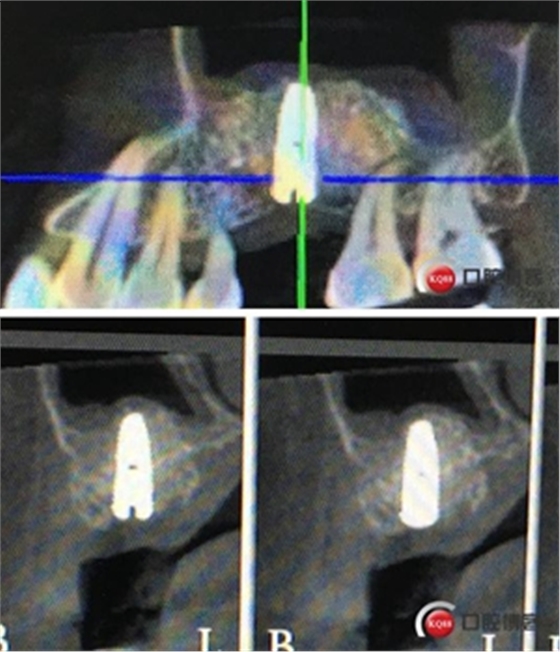

術(shù)后8個月,X光顯示骨量充足,密度明顯增加。

切開翻瓣。

植入一顆4.5x11.5mm長度植體。

植入后X光片。

半年后修復(fù)。